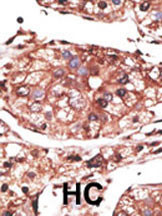

Formalin-fixed and paraffin-embedded human cancer tissue reacted with the primary antibody, which was peroxidase-conjugated to the secondary antibody, followed by AEC staining. This data demonstrates the use of this antibody for immunohistochemistry; clinical relevance has not been evaluated. BC = breast carcinoma; HC = hepatocarcinoma. |